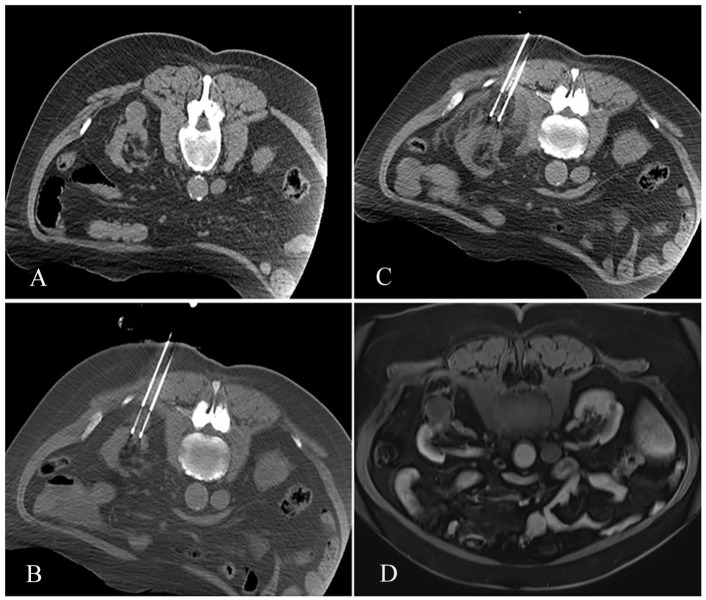

Abstract Image